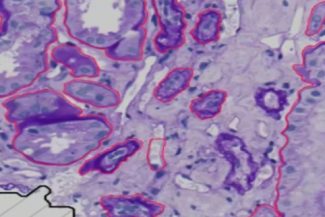

this image shows tubulus and PTC and how they connected

First training I did on the file IgA_PAS_008.czi scene 1, I use AI model for annotations and the ruselts its good and its show on the image the AI its able to annotate big object and separated and exclude the small area between the object 1. and its annotate the whole object as you can see in the second note the object has a different color but the AI its annotated like one object and that is correct .

After that I validate another region and its look so good in this image in below that the AI can annotate a complex object